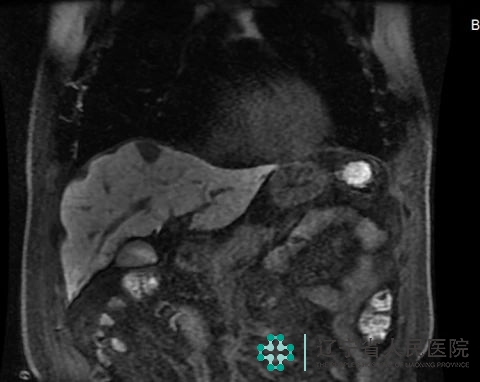

8月25日,我院普外六科(胆胰外科)收治一名乙状结肠癌根治术后10月肝转移的患者,由于转移灶位置特殊——位置深于肝脏VIII段,离心脏近,常规经腹入路,游离肝脏范围广,手术难度大。

经讨论研究,针对该患者适合实施个体化治疗方案——行经胸腔镜肝转移癌切除术。胸外科副主任医师杨海涛协助卜献民副院长于胸腔镜下打开膈肌,在术中超声的指引下确定肿瘤位置,充分暴露肿瘤,顺利进行了肝部分切除术。